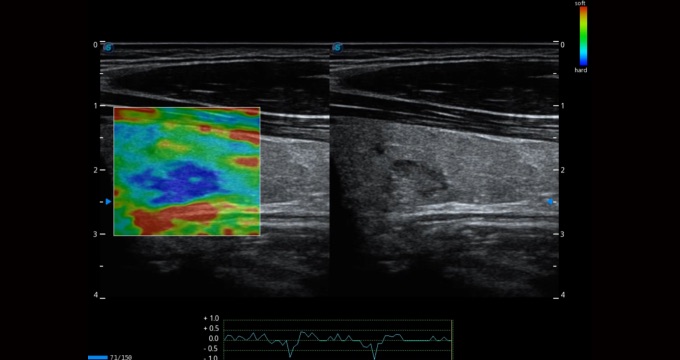

小器官應(yīng)用

彈性成像支持多把探頭,滿(mǎn)足全面的臨床應(yīng)用。無(wú)需高頻度外力作用可真實(shí)反映組織的形變,具有良好的重復(fù)性,幫助醫(yī)生早期洞察潛在的病理學(xué)特征。